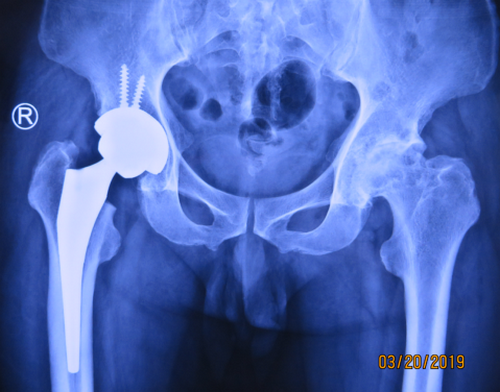

在术前,邱东新手术团队一如既往地对王师傅的情况进行了充分的评估,缜密的准备,制定了科学细致的手术方案。一切准备就绪后,手术如期进行,麻醉、切口、止血、假体测试、恢复腿长、假体安装、缝合切口……虽然手术难度比一般全髋关节置换要大了许多,邱东新手术团队1.5小时便完成了手术。手术很顺利,也很成功。

术后,在加强对患者基础护理的同时,关节科还积极开展了个性化的快速康复计划,预防各种并发症,促进患者恢复。在关节病区医护人员的精心治疗护理下,王师傅恢复得很好,术后两天便能下床行走,术后一周就出院了。出院前,王师傅感慨地说,早知道恢复得这么快,就不用吃这么多年的苦了!等我回家恢复两天,再过来把另一条腿的手术也做了。